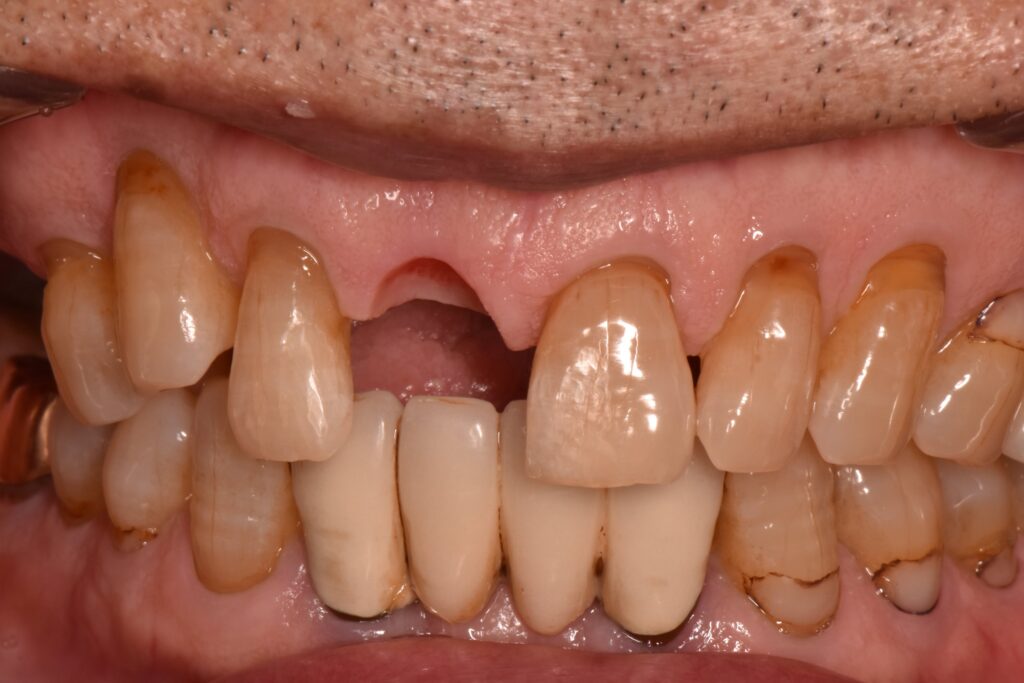

歯ぐきが綺麗に治癒するとこのように歯ぐきが凹んだ形となります。

片方の裏側だけに支えを持たせて、接着を行いました。支えとなっている部位はほとんど削らずに治療をしています。

抜歯直後から治療を行ったことで可能な限り審美的に治療を行うことができました。

接着ブリッジによる治療は、脱離するリスクは報告されていますが、長期に生存することが論文的に証明されています。歯をほとんど削っていないことは、とても大きなメリットだと思います😊